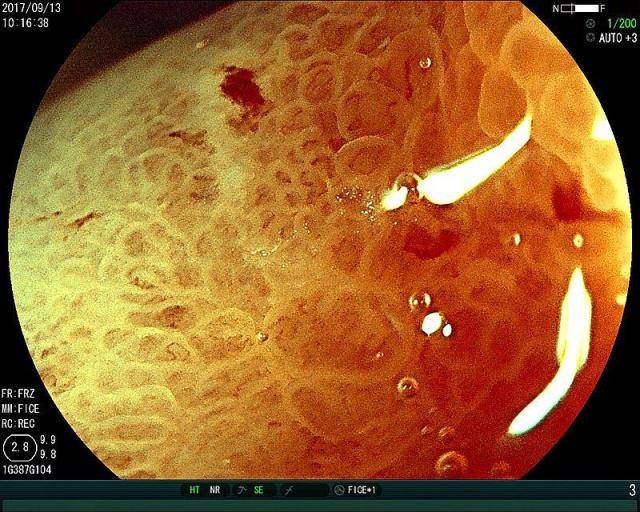

胃癌的发展分为四个阶段,因为这个胃壁是分为五层的,胃癌一阶段,癌组织起源粘膜的上皮组织,在胃粘膜下,这个叫做“早癌”,这个阶段,癌组织没有突破胃粘膜,这个时候癌组织就是米粒大。

然后会尽一步发展为胃癌二阶段,癌组织由米粒大又变大了一点点,但是还是没有突破肌层,在“早癌“出现,到二阶段,因为癌组织还没有突破肌层,所以人是没有任何主观感觉的,只能靠“胃镜”发现,所以只能靠自己主动去检查。这个阶段能及时处理,基本都可以痊愈。